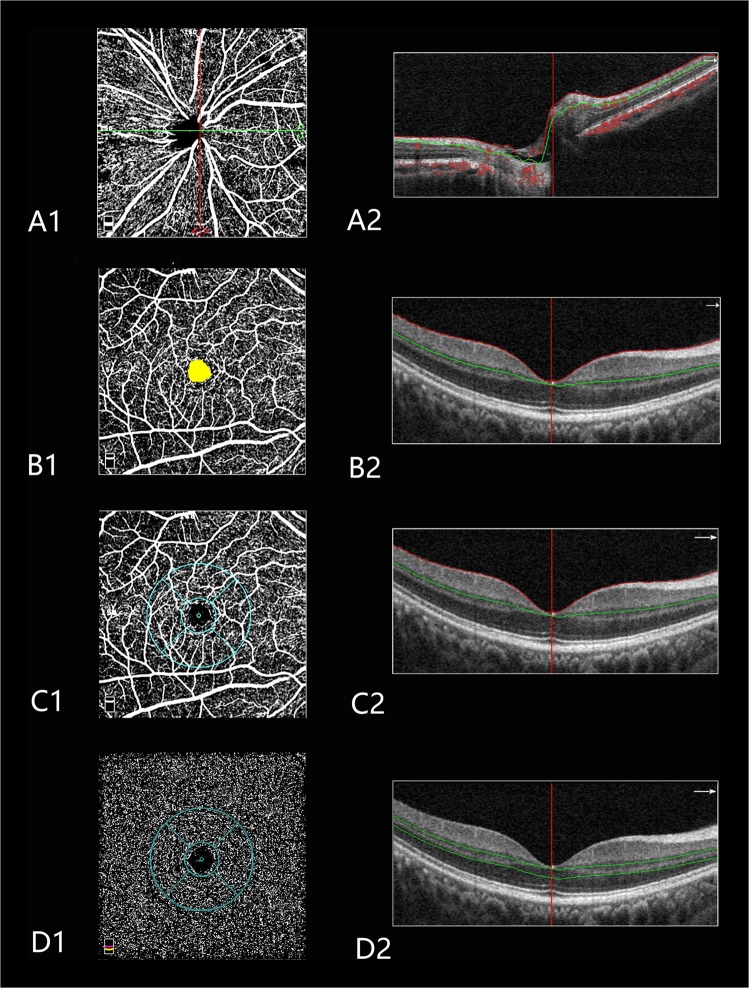

The angioflow vessel density was expressed as a percentage of the measured area and measured using the commercially unreleased software (version 2016.1.0.23). In this study, the peripapillary vessel density was measured in radial peripapillary capillary (RPC) layers (Fig. 1A1, A2). The foveal avascular zone (FAZ) area was outlined and automatically measured using the contained software (Fig. 1B1, B2). The parafoveal vessel density was measured in two layers, including the superficial and deep layers (Fig. 1C1, C2, D1, D2). Littman and the modified Bennett formulas were used to correct the area of FAZ induced by AL variation [18]. The exclusion criteria applied to the OCTA scans were a signal strength index <40 and images with segmentation errors or residual motion artifacts.

Fig. 1.

Peripapillary and macular perfusion were measured using optical coherence tomography angiography (OCTA) scans of the emmetropic eye. A1 Peripapillary angioflow density map of the radial peripapillary capillary layer. A2 The boundaries used for segmentation are indicated between the red and green lines on the cross-sectional OCTA reflectance. B1 Foveal avascular zone of the superficial layer. B2 The boundaries used for segmentation are indicated between the red and green lines on the cross-sectional OCTA reflectance. C1 Macular angioflow density map in the superficial layer. The sectors for measurements include the following: temporal, superior, nasal, and inferior. C2 The boundaries used for segmentation are indicated between the red and green lines on the cross-sectional OCTA reflectance. D1 Macular angioflow density map in the deep layer. The sectors for measurements include the following: temporal, superior, nasal, and inferior. D2 The boundaries used for segmentation are indicated between two green lines on the cross-sectional OCTA reflectance